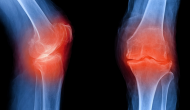

昨天和今天FDA的關(guān)節(jié)炎和藥物安全部門(mén)分別組織專(zhuān)家組討論了輝瑞和禮來(lái)的非阿片受體止痛藥、NGF抗體tanezumab用于骨關(guān)節(jié)炎的上市申請(qǐng),關(guān)鍵問(wèn)題是風(fēng)險(xiǎn)評(píng)估和管理計(jì)劃(REMS)不能有效降低關(guān)節(jié)損傷危險(xiǎn)。結(jié)果專(zhuān)家組以19票反對(duì)、1票支持認(rèn)為這個(gè)藥物風(fēng)險(xiǎn)、尤其是長(zhǎng)期用藥風(fēng)險(xiǎn)無(wú)法有效控制,支持的一票來(lái)自消費(fèi)者代表。這個(gè)一度被認(rèn)為是止痛領(lǐng)域新獅子王的產(chǎn)品面臨無(wú)法上市的窘境。